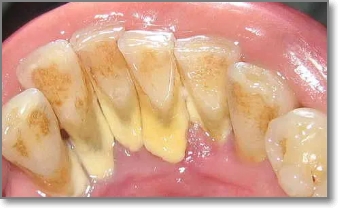

치석은 오랜 시간 쌓이면서 잇몸과 치아 사이를 가리고 있던 돌 같은 물질입니다. 이 치석이 갑자기 떨어지거나 스케일링으로 제거되면 그동안 가려져 있던 치아뿌리나 잇몸 틈이 드러나면서 공간(구멍)이 생긴 것처럼 보일 수 있어요.

이러한 치석 떨어짐으로 인한 구멍은 방치하면 더 큰 문제를 일으킬 수 있는데요. 이물질이 계속 끼고 충치나 잇몸염증으로 발전할 가능성도 높아지죠.

하지만 사실 구멍이 생겼다기보단 치석 아래에 있던 원래의 치아 구조가 드러난 것일 뿐이며 다만 이 공간이 음식물이나 세균에 노출되면 문제가 생기므로 그대로 방치하기보단 적절한 조치를 취하는 게 중요합니다.

치석 떨어짐 구멍 채우는 방법